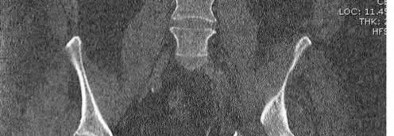

Figures A and B are the Lateral and AP radiographs of a displaced talar neck fracture with tibiotalar dislocation. Figures C and D are the post-reduction sagittal foot CT cuts that reveal a displaced talar neck fracture with medial

comminution.